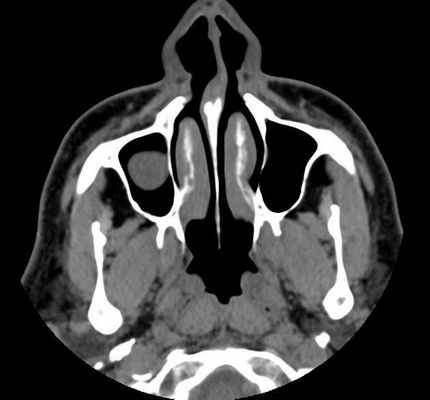

Компьютерная томография при гайморите

В некоторых случаях, помимо рентгена используется КТ гайморовых пазух носа. Это более информативный метод диагностики, который отличается своими преимуществами:

- Это наиболее достоверный способ обследования костных структур.

- Результат исследования – это трехмерный снимок, который позволяет рассмотреть обследуемую область под разными углами и во всех плоскостях.

- Процедура занимает меньше всего времени (если сравнивать с рентгеном и МРТ).

- Снимок получается максимально детализированным.

- Методика позволяет точно определить расположение и количество жидкости.

Отвечая на вопрос, что лучше проводить при гайморите – КТ или МРТ, нужно однозначно сделать выбор в пользу компьютерной томографии. Это обследование может проводиться даже при наличии коронок и имплантов, что невозможно при магнитно-резонансной томографии. К тому же, МРТ обладает наибольшей диагностической ценностью при обследовании мягких, а не костных тканей.

При помощи компьютерной томографии можно определить точную локализацию, размеры и особенности кистозного уплотнения.

В некоторых случаях может потребоваться проведение компьютерной томографии (КТ) при синусите. Данный метод исследования считается наиболее информативен и имеет несколько плюсов:

- Можно рассмотреть детально костную структуру.

- Возможность определения количества экссудата в пазухах носа.

- Получение объемного снимка в различных плоскостях.